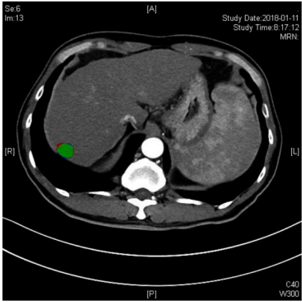

龙立强人工智能科技(苏州)有限公司,是一家致力于革命性医学影像解决方案的企业。公司的宗旨是推动医学界数字化革命,特别是在医学影像自动识别软件领域。我们的使命是为医院提供高效的数字化医疗解决方案。

通过医学影像自动识别软件

- 1、辅助提高基层医生诊断水平

- 2、改善患者等待影像报告时长,缩短患者候诊时间提高效率

- 3、改善医学影像误诊率高的问题

AI-CT医疗影像多脏器多种疾病一体式识别模型

0AI-MIR医疗影像多脏器多种疾病一体式识别模型

0" data-ckey="itemSubtitleFont" data-key="items">AI超声医疗影像多脏器多种疾病一体式识别模型

超声甲状腺癌自动识别软件在短时间、低数据量的环境中取得了非常惊人的结果。测试显示:灵敏度为99.4%,特异性约93%。这意味着该软件极大的防止病例漏报现象的发生。提供图片的医生认为诊断结果相当于人类医生诊断水平。

我们的算法对肿瘤良性恶性的判断正解率为92.9%,超过了合作医院先前合作的团队(该团队的正解率为90.3%),以及放射科医生(放射科医生的正解率为88.9%)。合作医院的研究团队也对这一结果十分震惊,开始对软件进行临床试验。